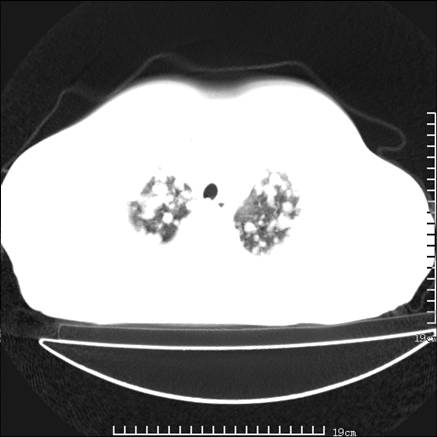

张男,75岁,干咳半年余,小便不利二年,b超检查前列腺增大,未见明显肿块;前列腺癌血生化检查多项指标明显增高。

双肺内多发转移瘤,纵膈淋巴结转移。来源前列腺?建议盆腔mri进一步检查。

双肺转移满了。

两肺广泛转移瘤。